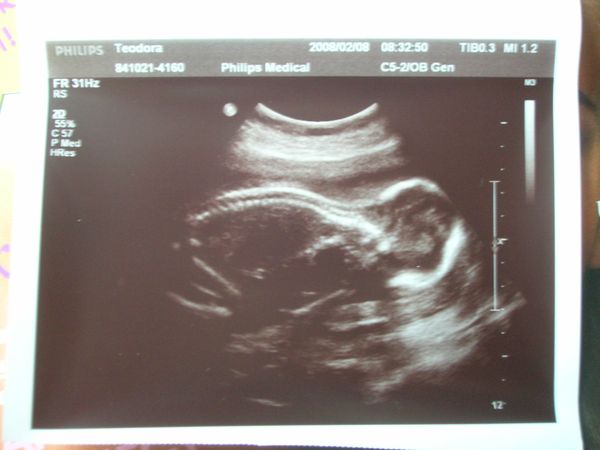

Én tegnap voltam 18 hetes genetikain ahol megerősítést kaptunk, hogy Dávidka Dávidka marad most már nincs mese

BPD:43mm THQ:39 mm ezeket mérték, az AFP értéke meg 1,21